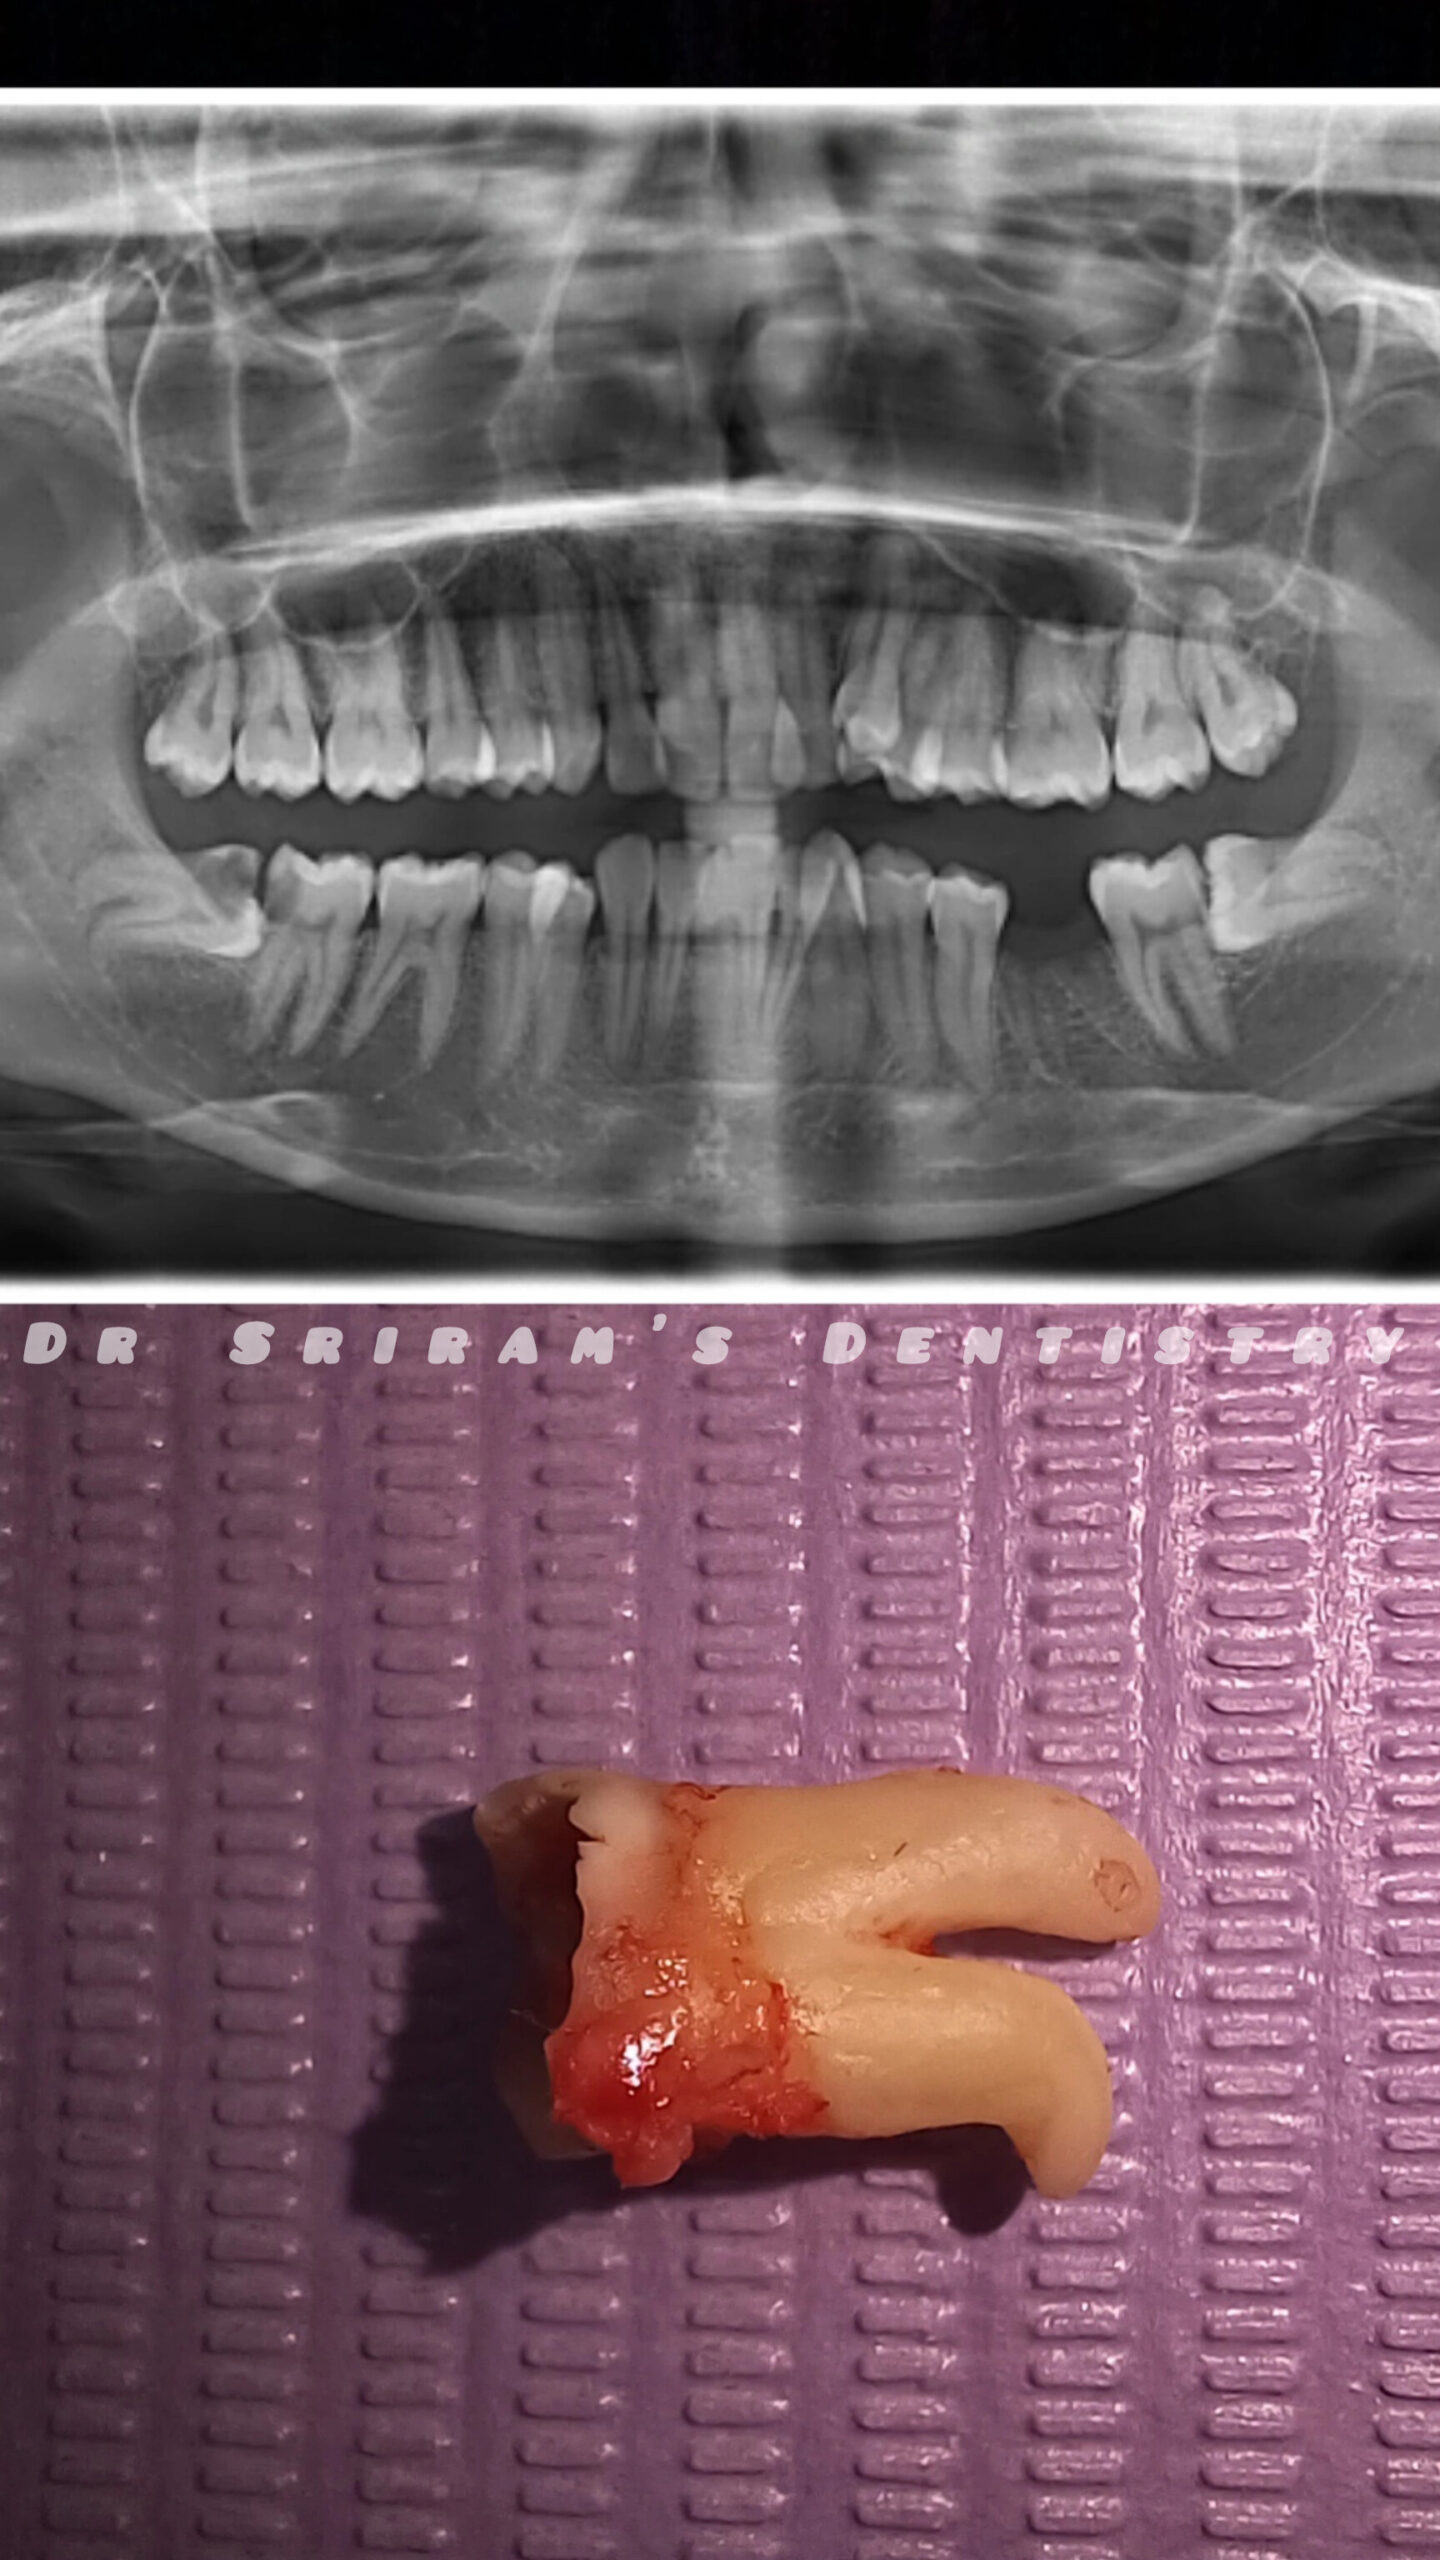

Gallery Home Gallery Pulpectomy Broken File Retrieval Root Canal Treatments Orthodontic Treatments Wisdom Teeeth Removal